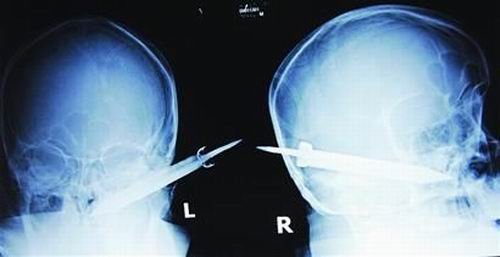

經(jīng)過檢查,醫(yī)生說這把長有10厘米左右的刀,從右耳窩上前方直接刺進(jìn)了鼻腔,離頜內(nèi)大動脈很近,刀卡在了骨頭中,要取出這把刀最怕大出血,萬幸的是這把三棱刀并沒有傷及大腦。

截至昨晚11時30分,患者頭部刀經(jīng)手術(shù)已取出,生命體征平穩(wěn)。(芮瀟瀟)